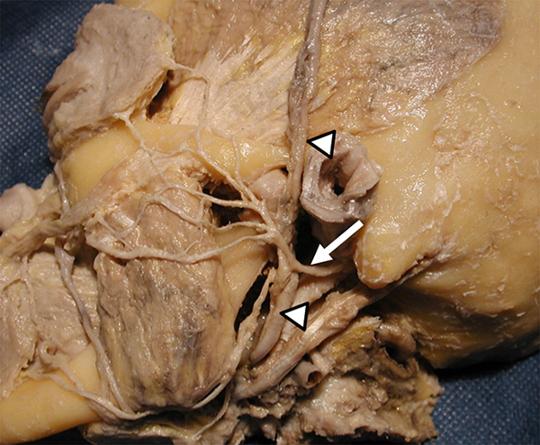

Preparado anatómico, vista posterior de la región petroclinoidea izquierda, donde se observa el nervio abducens (flecha larga), atravesando el canal de Dorello. Se remarcan el ligamento petroclinoideo (cabeza de flecha), el nervio trigémino (flecha corta) y arteria carótida interna (estrella).

Corte axial de RM en imágenes ponderadas en T2. Paciente que consultó por parálisis del sexto nervio craneal izquierdo e hipoestesia facial ipsilateral. Se observó una lesión que compromete la región petroclival izquierda (flecha), la cual es marcadamente hiperintensa en imágenes ponderadas enT2 (probable componente cartilaginoso). Correspondió a un condrosarcoma.